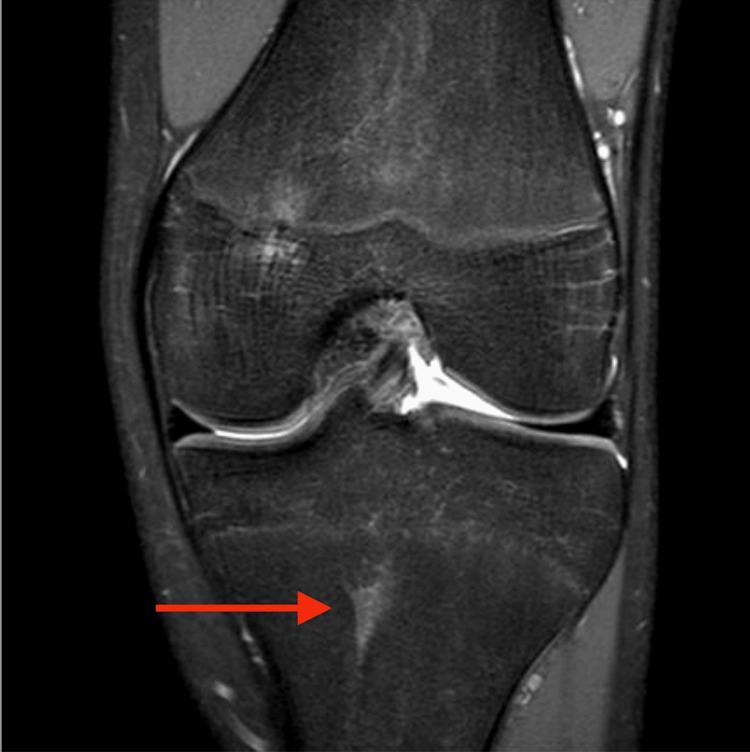

Focal periphyseal edema (FOPE) is a normal physiological finding that is often incidentally discovered on MRI of the knee. FOPE zones are areas of periphyseal edema typically observed near the time of physeal closure. This common physiologic phenomenon is related to changes in the distribution of forces around the physis as it closes during adolescence, occurring more frequently in females between 11 and 14 years of age. The condition may be associated with pain or may be asymptomatic. It is often mistaken for pathological bone marrow edema or a Salter-Harris fracture. We present the case of a 14-year-old female patient with chronic knee pain and no history of trauma. MRI revealed two FOPE zones in the distal femur, with no other abnormalities. The patient was managed conservatively with observation and physical therapy, resulting in gradual symptom resolution. This case reinforces that FOPE should be recognized as a normal variant in adolescent knees to avoid misdiagnosis and unnecessary treatment.

https://cdn.ncbi.nlm.nih.gov/pmc/blobs/8a04/12339012/cb284c699c26/cureus-0017-00000087790-i01.jpg